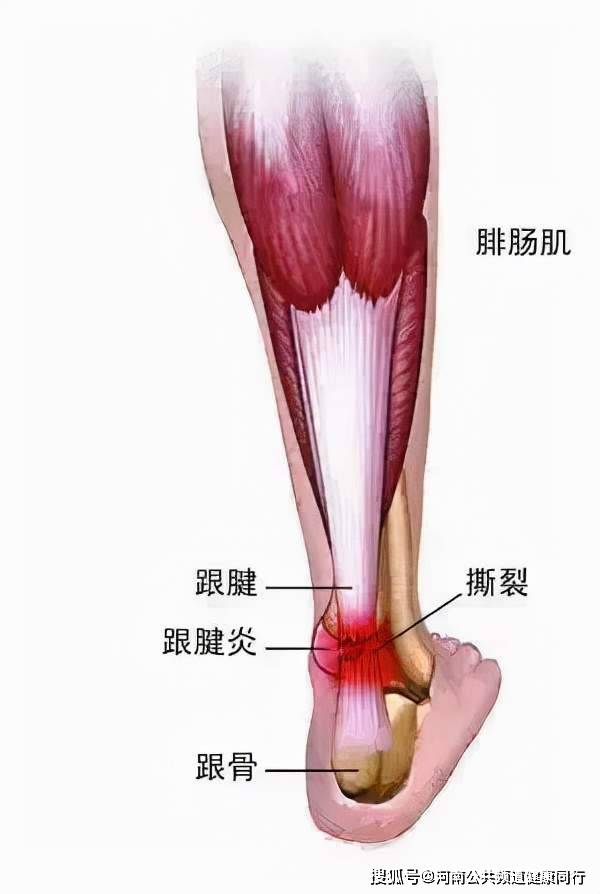

"坚韧"的跟腱也会"脆弱"——河南省骨科医院明晓锋_运动

图片尺寸600x894